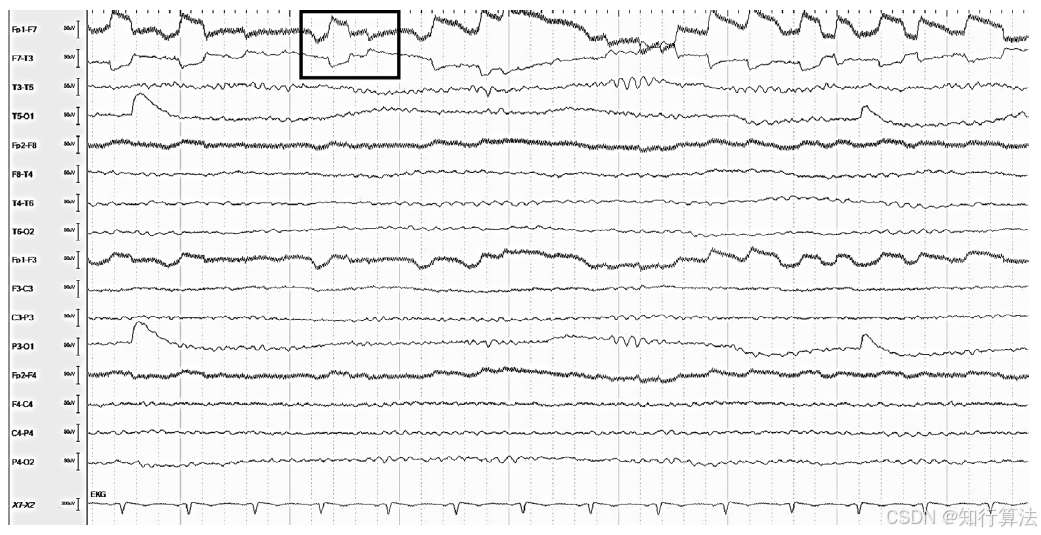

波形特征:清醒期可见规则的水平眼动(图9);REM睡眠期可见快速眼动(图11);困倦期出现慢速“划船样”眼动(图12)。

临床意义:

水平眼震可被误认为发作期活动(图10:左眼水平眼震在F7导联的伪迹)。

外直肌棘波(F7/F8的小尖波)常预示水平眼动。

处理方法:注意与癫痫性眼动鉴别,结合临床状态判断。

图12:疲倦状态下缓慢的扫视眼动干扰(F7/F8 通道)